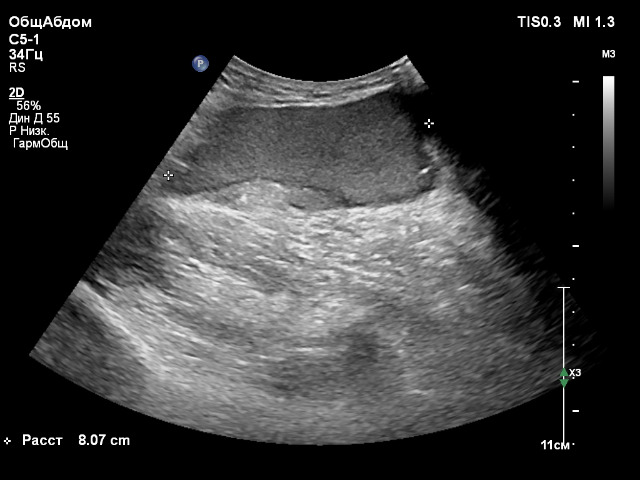

Мужчина, 61 год, пришел с "шишкой" в ягодице. Ощущает ее достаточно давно, говорит, что, возможно, появилась после инъекции. Расположена в ПЖК, четкие выраженно неровные контуры, дает "отроги" в виде пальцев, с такими же четкими контурами, в окружающий жир. Образование полностью аваскулярное, гипоэхогенное за исключением гиперэхогенного участка у одного из краев, ок. 30х15 мм, с нечеткими контурами, неправильной формы, тоже сравнительно однородного и аваскулярного. Посоветуйте, что может быть?